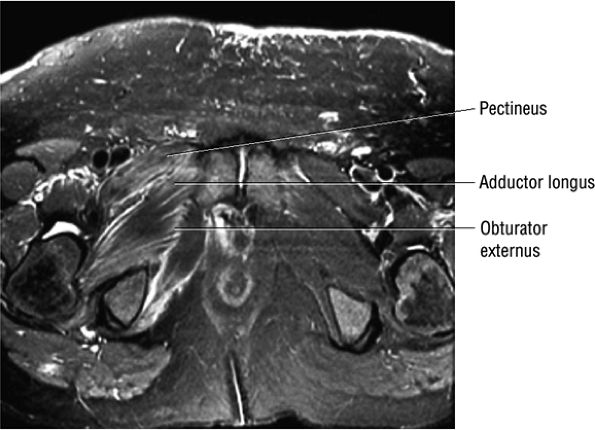

FIGURE 3.109 ● Grade 1 muscle strain of obturator externus, adductor brevis adductor longus, and pectineus muscles. Axial FS PD FSE image.

FIGURE 3.106 ● Bilateral adductor longus grade 1 muscle strain with diffuse hyperintense muscle edema. Coronal FS PD FSE image.

FIGURE 3.11 ● PECTINEUS The pectineus muscle adducts, flexes, and medially rotates the thigh. The adductor muscles, the pectineus, and the gracilis represent the muscles of the medial aspect of the thigh.

FIGURE 3.12 ● ADDUCTOR LONGUS The adductor longus adducts and assists in the flexion of the thigh. The adductor group muscles (longus, magnus, and brevis) originate at the symphysis pubis and inferior pubic ramus and insert on the linea aspera of the femur.